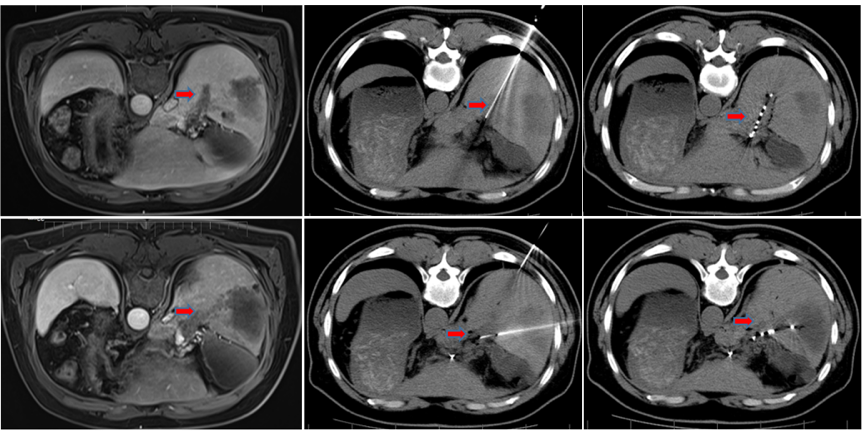

2020年12月7日行门脉粒子植入术(图4)。并后续给予TACE治疗,术中用药:奥沙利铂150mg 雷替曲塞4mg 碘油3ml。术中造影可见肝右叶肿瘤仍有少部分染色,而门脉右支分布的区域可见门脉癌栓肿瘤染色。

图片

图4.2020年12月7日门脉粒子植入术